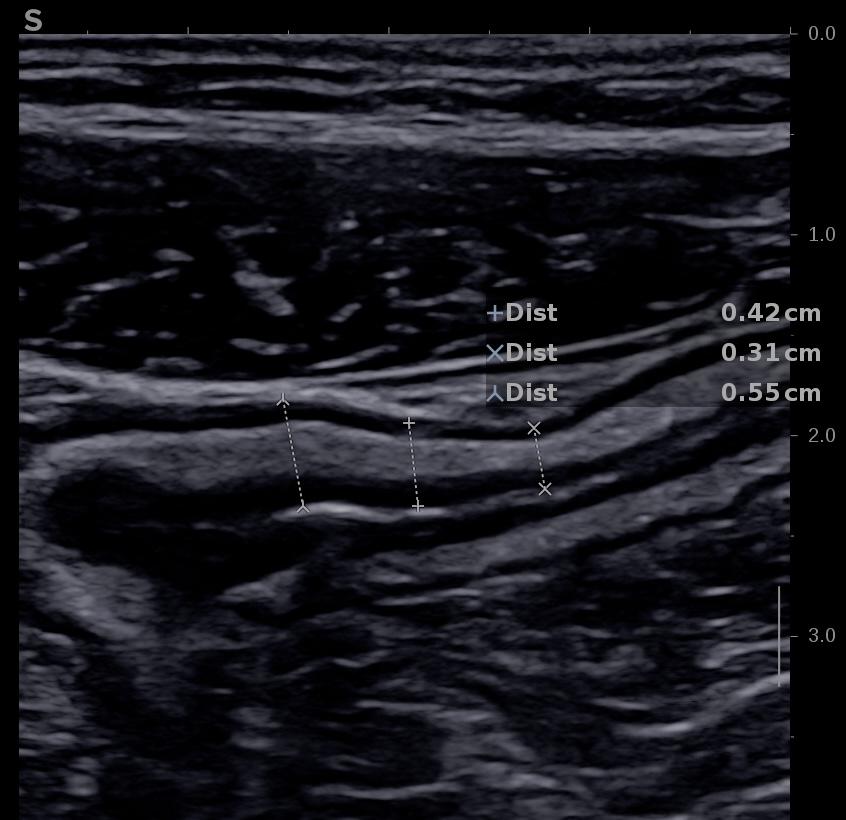

L'épaississement se mesure entre la muqueuse (hypoéchogène) et la musculeuse (hypoéchogène),

Ci dessous même portion avec et sans compression douce.

Il faut faire la moyenne de plusieurs mesures (≥3) en coupe longitudinale et transversale